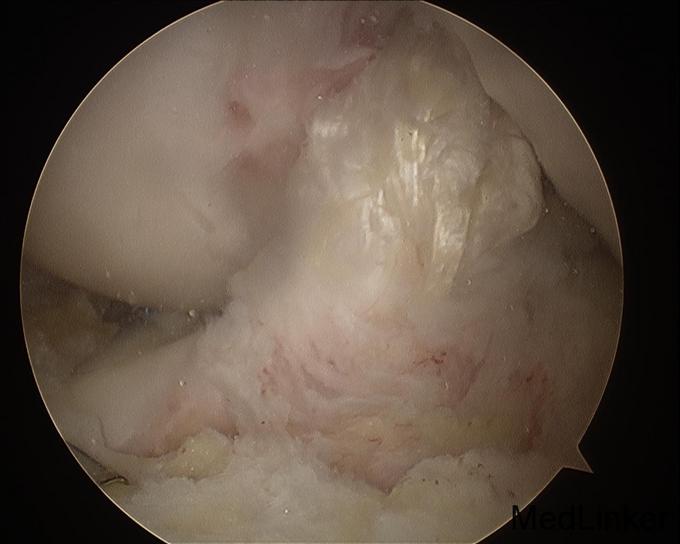

诊断:左膝前交叉韧带重建术后,左膝半月板损伤。 治疗:左膝内固定取出术+左膝关节镜下探查+左膝前交叉韧带皱缩+内侧半月板成形术

随访:患者术后扶拐行走2周。2周后活动度恢复正常,亦恢复正常行走。 讨论:该患者为前交叉韧带自体肌腱重建术后9年,难得有机会进行second look。术中发现重建韧带形态完整,但纤维松散,术前查体亦有松弛现象。术中予以紧缩处理后,术后松弛度明显改善。